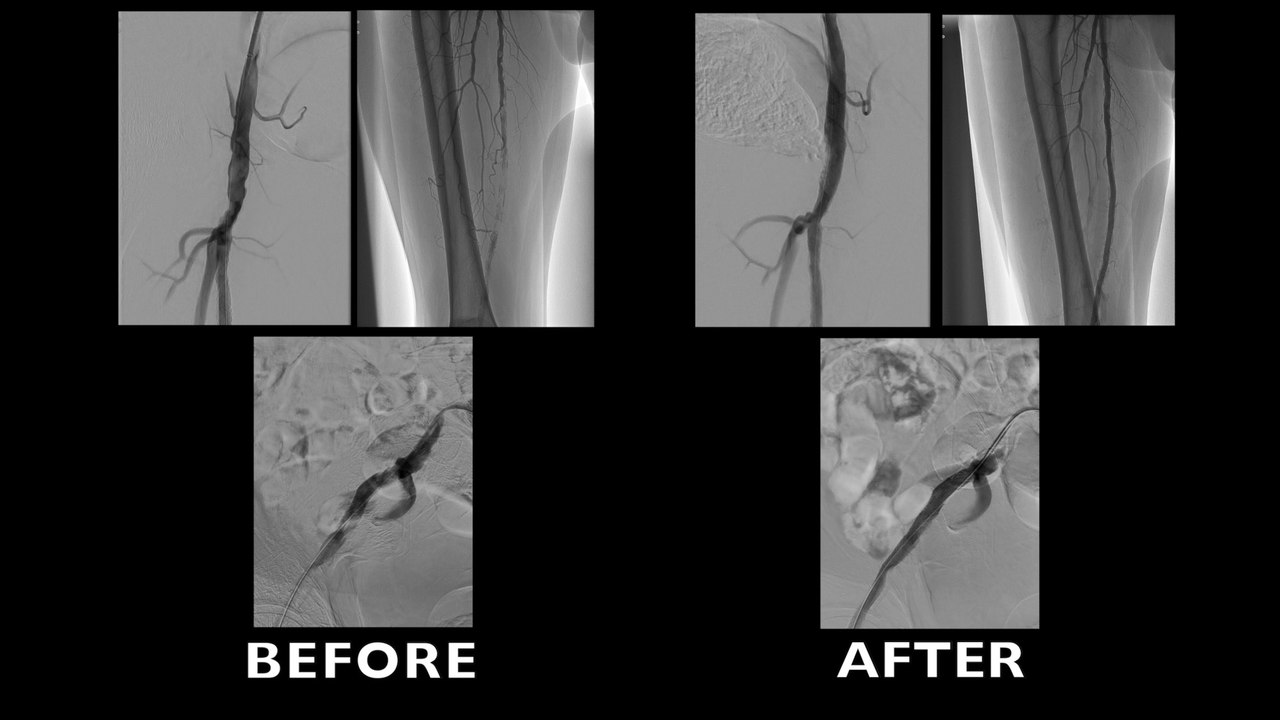

SUPERSUB: Subintimal approach and Supera Stent for SFA-POP TASK C and D lesions in CLI patients

Jet stream Atherectomy System for popliteal artery occlusion